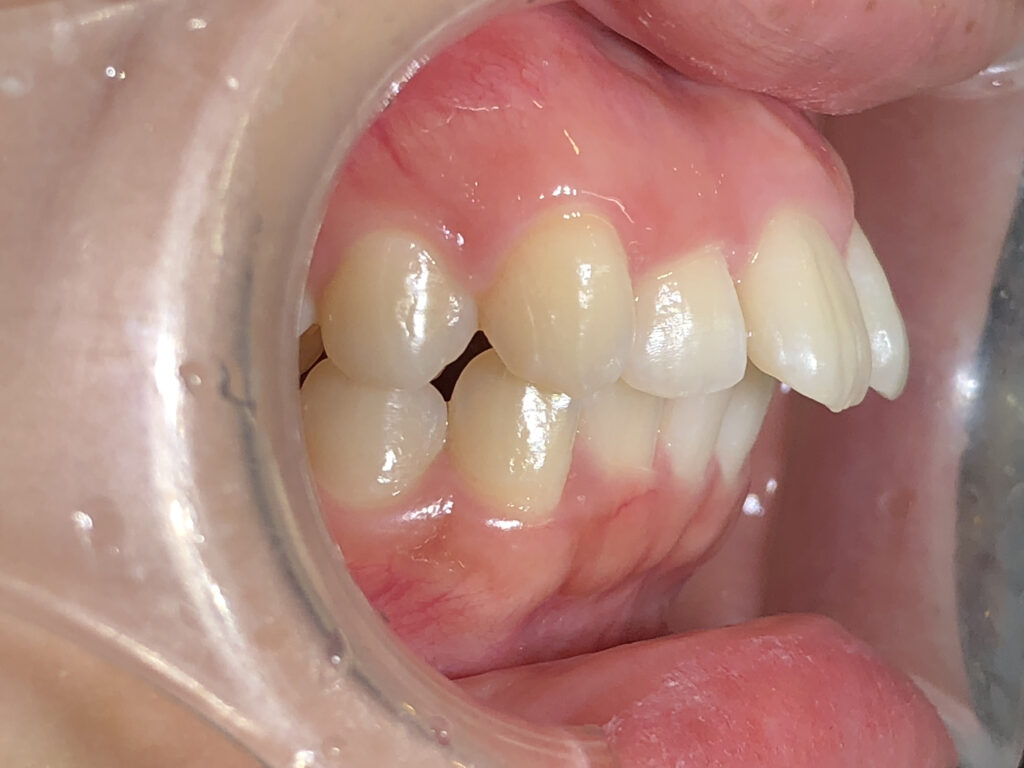

オーバージェット

治療前

治療後